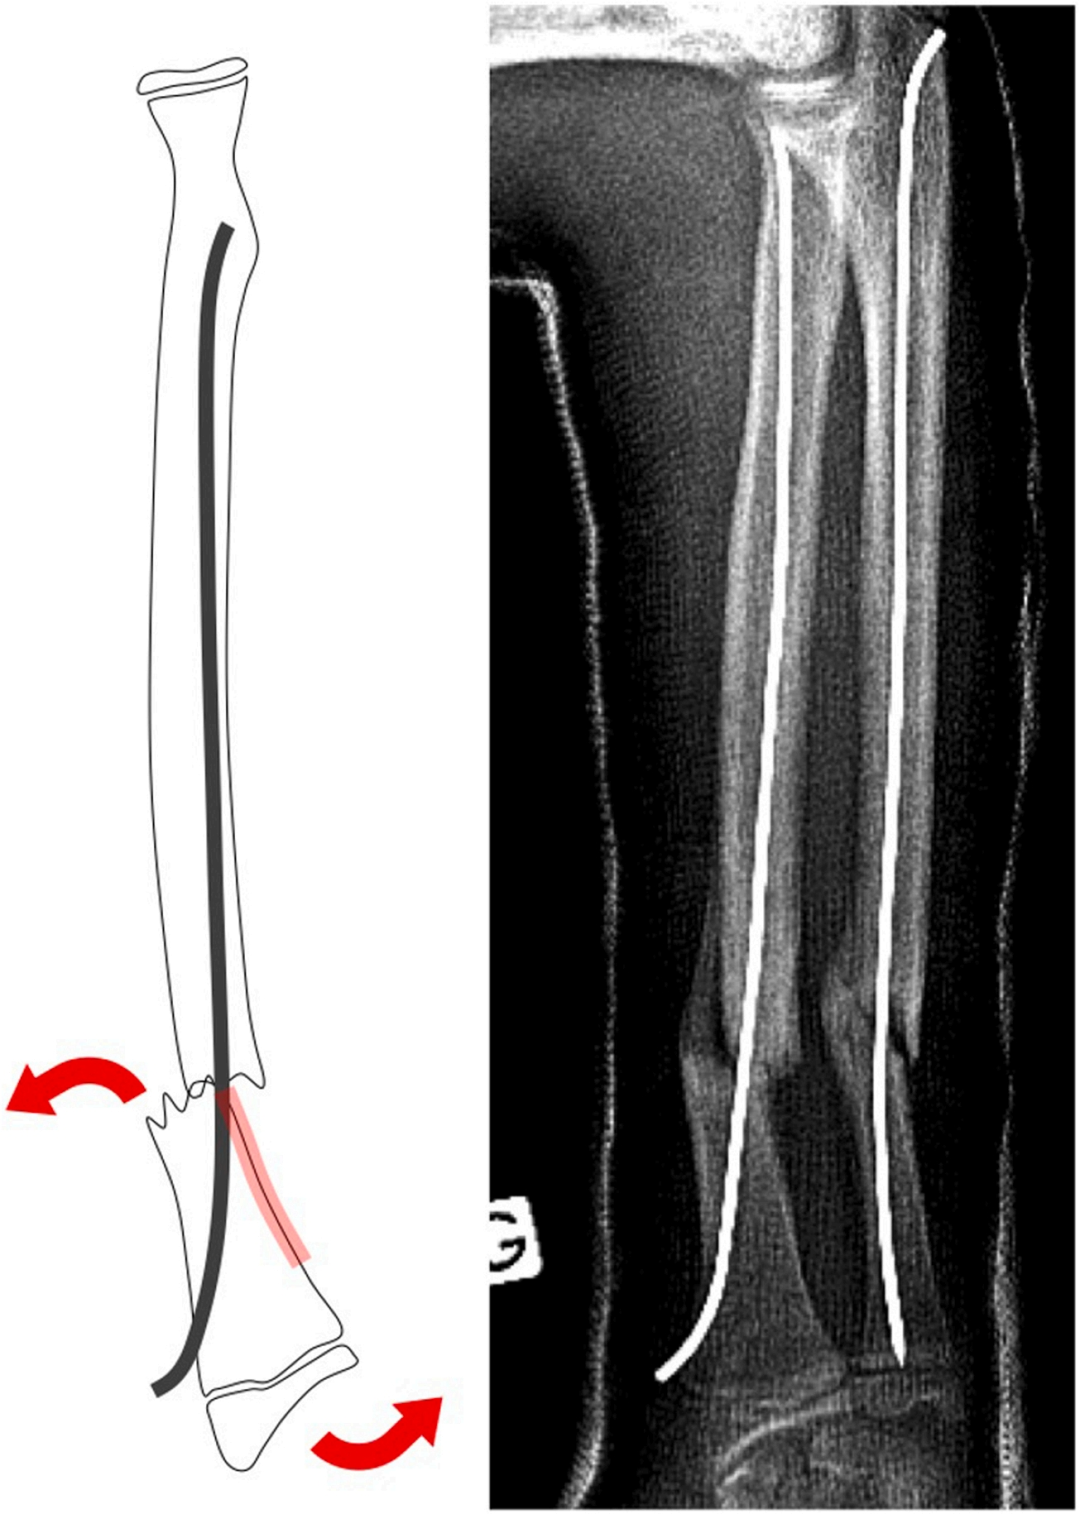

将S形结构进行如下折弯:使近端反折点支撑于桡侧骨皮质壁,S形的斜向部分穿过骨折线,远端反折点随即在尺侧支撑于骨皮质,如下图: